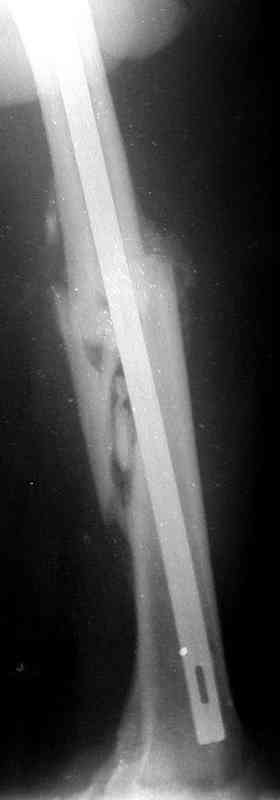

по его наружной поверхности послеоперационный рубец - рана зажила первичным натяжением. При измерении длины бедер обнаружено укорочение левого бедра на 4,5 см. На рентгенограммах этого бедра: ось конечности правильная, отмечается захождение основных костных фрагментов по длине, проксимальный конец штифта выступает слишком медиально и высоко относительно большого вертела, периостальная мозоль незначительна.22.12 - через 6 месяцев после операции, произведенной в ЦРБ, нами по поводу замедленно консолидирующего перелома левой бедренной кости с ее абсолютным укорочением под наркозом произведена операция: удаление штифта, закрытый блокирующий интрамедуллярный остеосинтез перелома левого бедра штифтом без рассверливания (UFN) длиной 40 см, диаметром 10 мм с блокированием только проксимальных отверстий (динамический остеосинтез). Наложен аппарат Илизарова на 4 полукольцах с целью удлинения укороченного бедра. Послеоперационное течение без особенностей. Ежедневно осуществляли дистракцию отломков на 1 мм. Через 3 недели после операции больной выпи-сан на амбулаторное лечение с продолжением дистракции отломков. В течение 1,5

месяцев дистракции укорочение левого бедра удалось полностью устранить. 22.02.00, т.е. через 2 месяца после повторного остеосинтеза, больному произведено дистальное блокирование штифта двумя винтами и демонтирован аппарат Илизарова. В течение 2 недель после операции больной ходил с помощью костылей, потом 2 недели с тростью. Опороспособность и функция оперированной конечности полностью восстановились через 4 недели после операции.